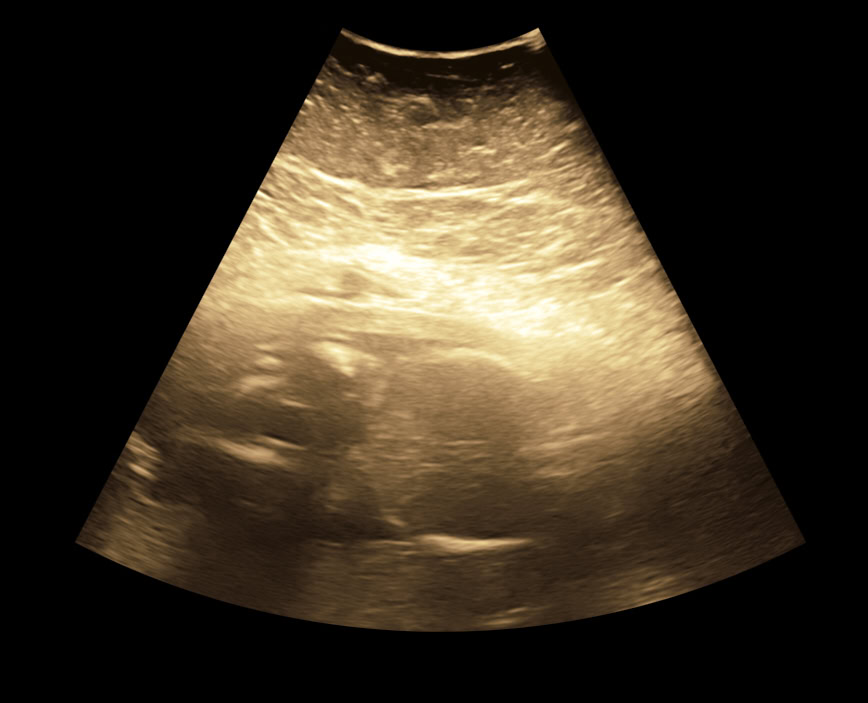

fetales Profil in der 24. SSW